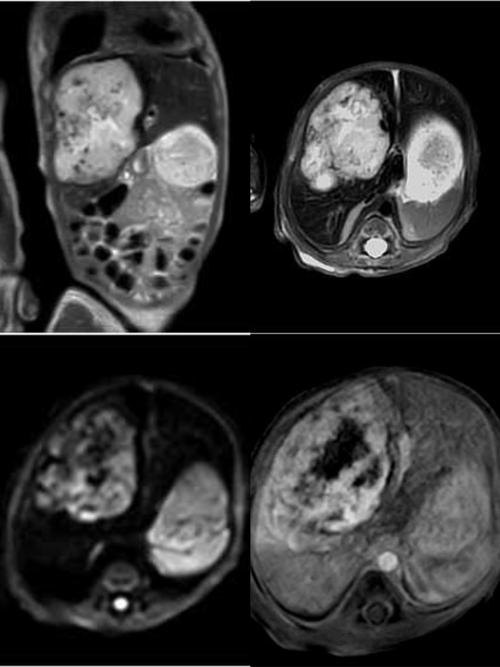

医生建议给10天大的新生儿做MRI,一定是出于非常明确的医学必要性,MRI是一种无创、无辐射的影像学检查,它能提供非常清晰、详细的软组织(如大脑、脊髓、肌肉、内脏等)图像,这是其他检查(如B超、CT)无法比拟的。

MRI是目前评估新生儿脑部及软组织结构最安全、最精确的工具之一,医生选择它,是为了给宝宝得到最准确的诊断,从而制定最合适的治疗方案。